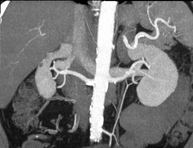

Prova diagnòstica no invasiva que consisteix en l'estudi de les artèries renals a través de l'obtenció d'imatges d'alta definició anatòmica mitjançant l'ús d'un equip de TC (Tomografia Computeritzada) i de contrast iodat. La qualitat de les imatges permet realitzar reconstruccions en 2D i 3D gràcies a estacions de treball especialitzades en l'estudi arterial. Està indicat en aquells pacients amb malaltia vascular (arteriosclerosi), en aneurismes d'aorta, en pacients amb dolor abdominal de possible origen vascular, en estudis prequirúrgics de lesions adjacents a l'aorta abdominal com a "mapa" vascular. La informació obtinguda de manera no invasiva és indispensable per als pacients que requereixen tractament percutani o quirúrgic. En aquells pacients que només requereixen seguiment de les lesions vasculars, aquesta tècnica és la tècnica no invasiva d'elecció juntament amb l'angio-RM. - Angio-TC Aorto-ilíac

Prova diagnòstica no invasiva que consisteix en l'estudi de les artèries renals amb l'obtenció d'imatges d'alta definició anatòmica mitjançant l'ús d'un equip de TC (Tomografia Computaritzada) i contrast iodat. La qualitat de les imatges permet realitzar reconstruccions en 2D i 3D gràcies a estacions de treball especialitzades en l'estudi arterial. Aquesta prova està indicat en aquells pacients que pateixen HTA refractària al tractament, en pacients amb lesions renals que tenen un mapa vascular prequirúrgic, etc. - Angio TC d'aorta-ilíaca